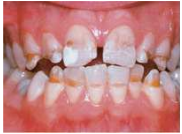

47.改善牙釉質發育不全(enamel hypoplasia)(如附圖)的美觀問題,下列治療計畫何者最恰當? (A)輕微磨除(microabrasion) (B)深度磨除(macroabrasion) (C)活性漂白(vital bleaching) (D)陶瓷貼面(porcelain veneers)